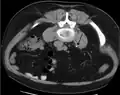

Otherwise a noncontrast helical CT scan with 5 millimeters (0.2 in) sections is the diagnostic method to use to detect kidney stones and confirm the diagnosis of kidney stone disease.[16][57][61][66][7] Near all stones are detectable on CT scans with the exception of those composed of certain drug residues in the urine,[59] such as from indinavir.

Three-dimensional reconstructed CT scan image of a ureteral stent in the left kidney (indicated by yellow arrow), with a kidney stone in the inferior renal pelvis (highest red arrow) and one in the ureter beside the stent (lower red arrow)